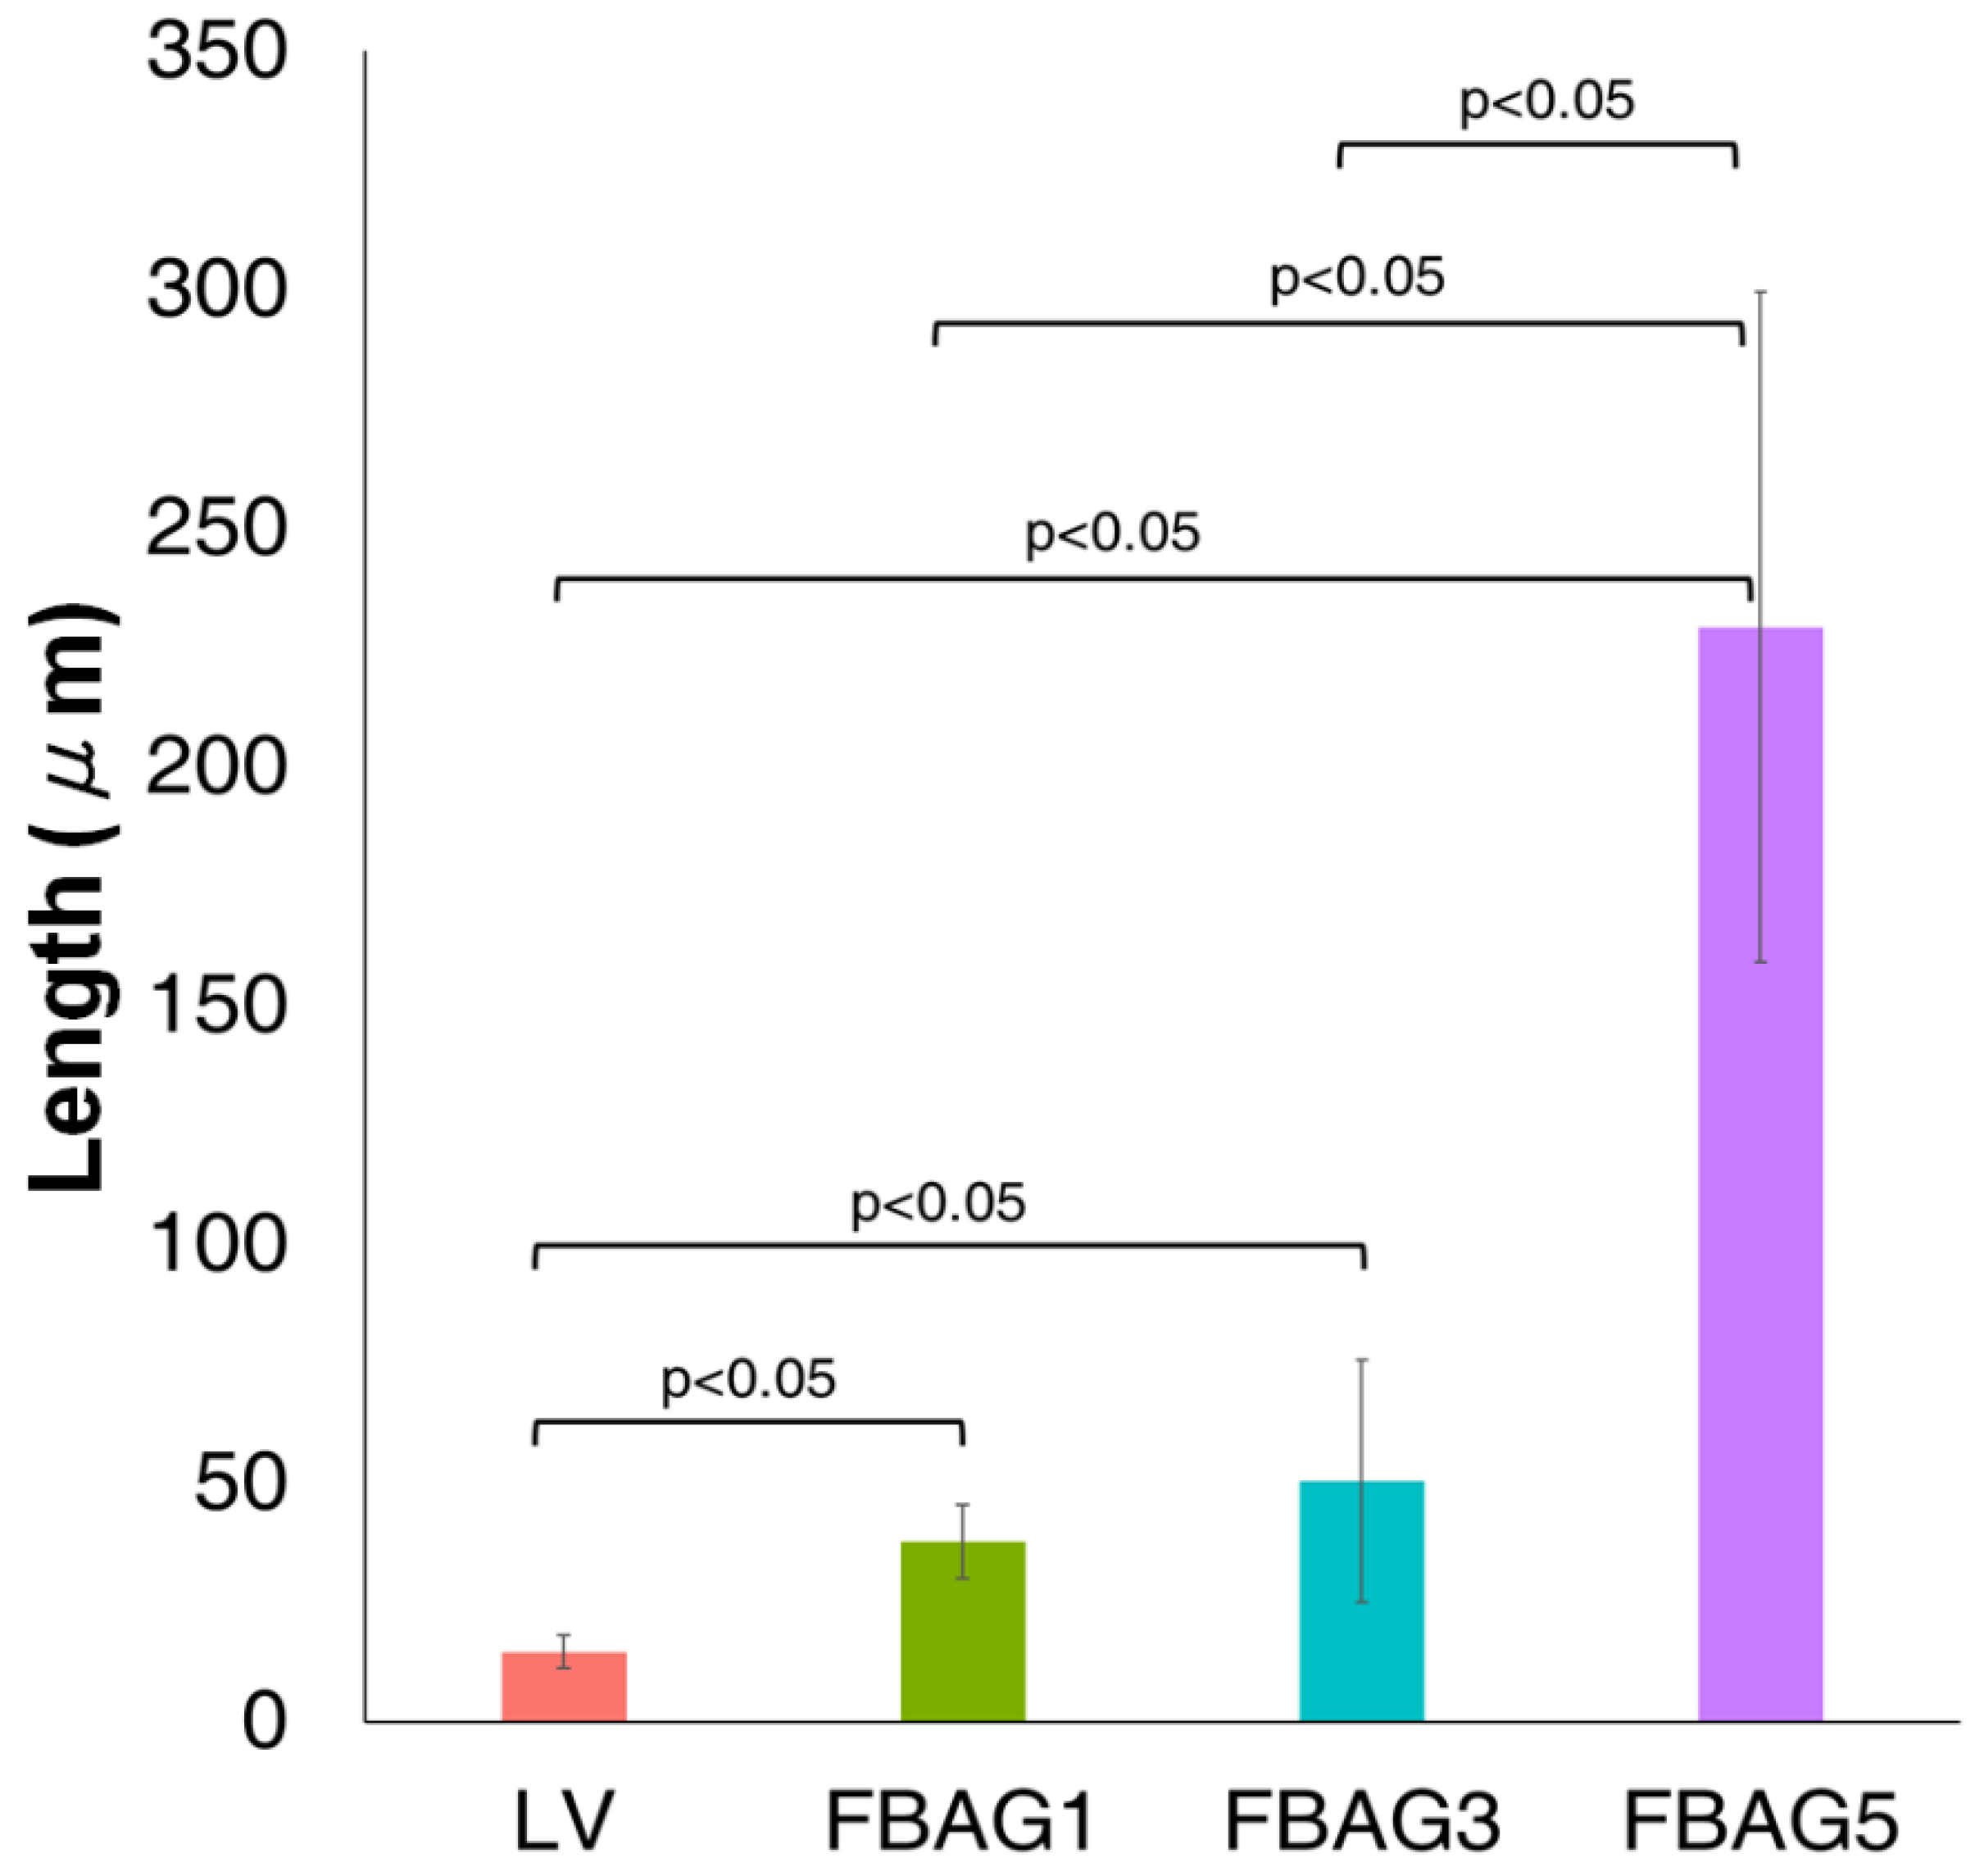

3.8. Anti-demineralization